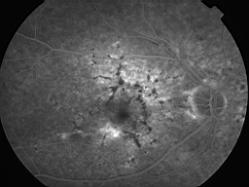

ASSOCIATION STRIES ANGIOIDES ET DYSROPHIE MACULAIRE RETICULEE

NEOVASCULARISATION